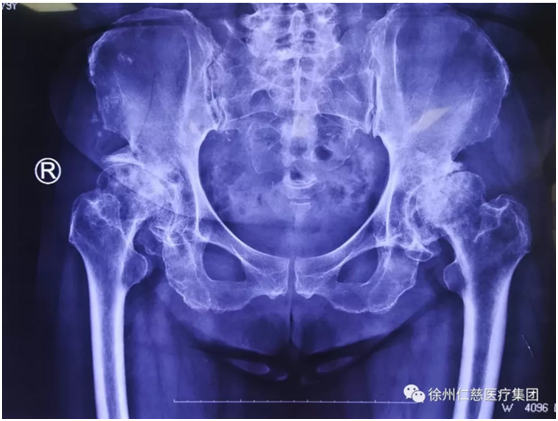

郝醫(yī)生一聽他這么能喝酒,點(diǎn)點(diǎn)頭,安排他攝片,果然,顯示右側(cè)股骨頭壞死,需要做全髖關(guān)節(jié)置換。

(術(shù)前)

“喝酒要適量,以后得少喝酒啦,你這股骨頭壞死就是喝酒喝的。”郝醫(yī)生安排李師傅住院,一邊叮囑。